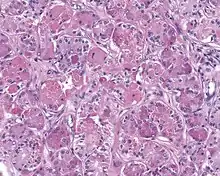

Low power H&E stained image of parotid gland sclerosing polycystic adenoma

When reviewed by a pathologist, the findings are quite similar to fibrocystic changes of the breast, although they are different enough, that it is now recognized to actually represent a true neoplasm (clonal proliferation) through various studies.[5] Specifically, the lesions are usually well-circumscribed, containing lobules of haphazardly arranged ducts, myoepithelial cells, and acini that have abundant sclerosing or hyalinized fibrosis. Apocrine change is quite common in the ductal cells.[6] The ducts range from small ductules to cystically dilated spaces (more than 4 striated duct-widths across), often containing products of secretion or reactive histiocytes. A very curious and characteristic finding in all of the lesions is the presence of bright pink (eosinophilic) acinar granules (which are altered zymogen).